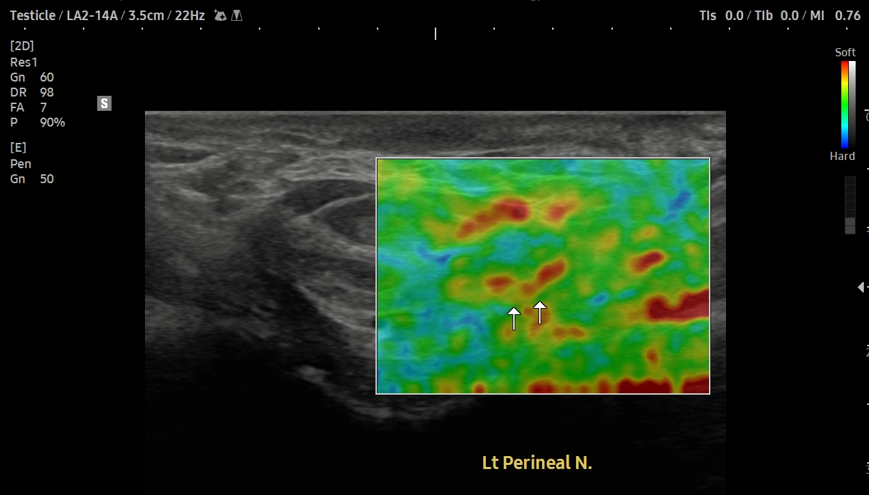

- 치료기간 : 25. 7 . 15 ~ 25. 11 . 18

- 치료횟수 : 25(5cycle) 회

[후기]

치료 전

치료 후